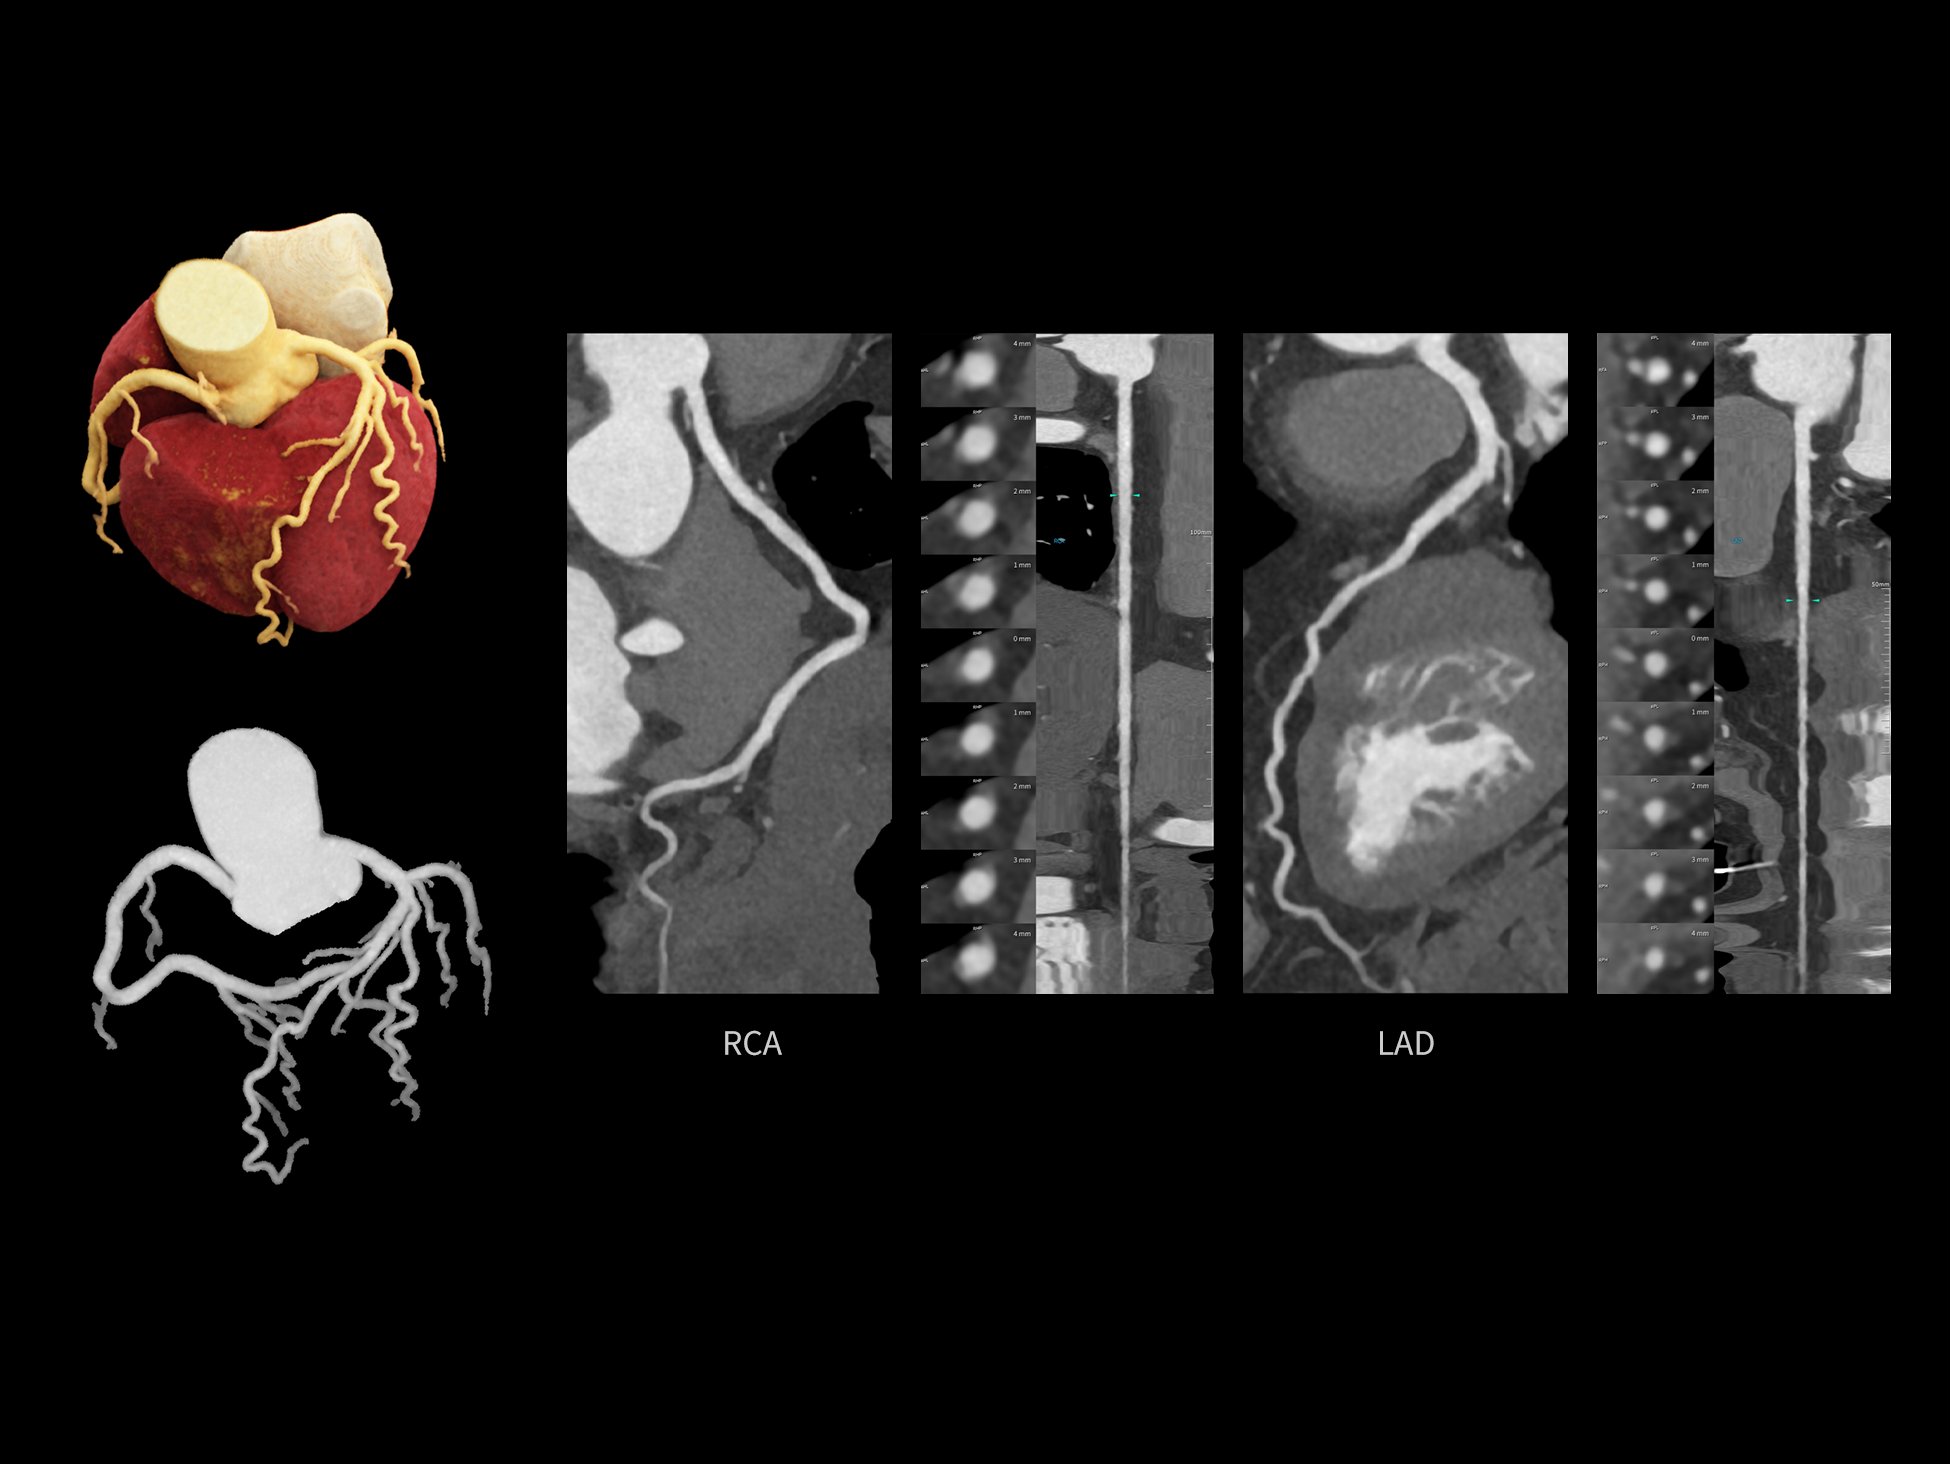

uCT SiriuX® 依托16cm超宽探测器与双源能谱技术,实现真正意义上的全身高清能谱成像。单次扫描同步获取灌注、能谱等多维定量参数,精准解析组织特性与病灶成分,为临床决策提供更深层次的诊断依据。

能谱成像可揭示丰富的物质与能量信息,其临床价值的充分释放有赖于完善高效的后处理分析平台。uCT SiriuX® 提供全面能谱高级分析工具,覆盖心血管、肿瘤、神经、骨科等多类临床场景。平台支持动脉增强分数分析(AEF)、细胞外容积分析(ECV)、肿瘤同源性分析、肺栓塞分析、骨髓水肿分析等多项评估,并提供多达10种基物质对成像,为精准诊断与科研探索提供坚实支撑。